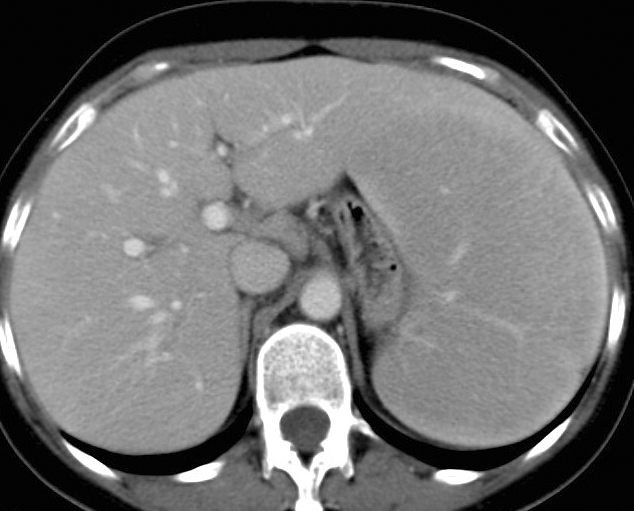

Gallery Mediastinum Lymphoma 3b

3b